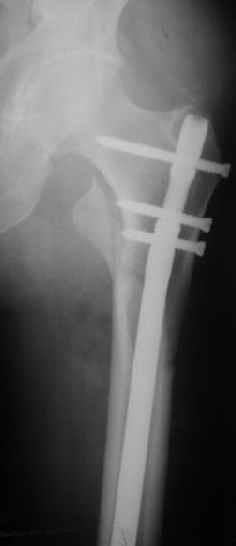

> При межвертельных переломах с цефаломедуллярными гвоздями бывает,

> что проксимальый винт проходит или черед периферический отломок, или

> прямо над ним. И если остался диастаз, то этот винт при осевой

> нагрузке не дает сблизиться отломкам. Пример остеосинтеза в застарелом

> случае в приложении. В качестве предупреждающей меры можно долотом

> разрушить латеральную стенку дистального отломка под винтом.

Конечно, мы не синтезируем остеопорозые вертельные переломы согласно прилагаемому примеру, винты 6 мм вырежутся. Но у более молодых при хорошем качестве кости такие или подобные гвозди с поперечным расположением винтов вполне применимы для меж- и подвертельных переломов.

Это было года 2,5 назад, мы тогда еще уточняли возможности шинирования с угловой стабильностью гвоздем с поперечным расположением винтов при переломах проксимального отдела бедра. Пациенту не пришлось приобретать намного более дорогой рекон или проксимальный гвоздь. В приложении еще несколько примеров применения того гвоздя при высоких переломах бедра, в том числе с более латеральной точкой входа. Гвоздь изгибаем для этого.